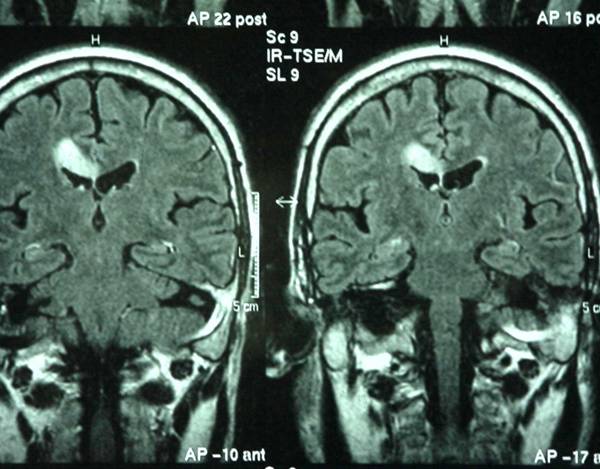

Navegar por la vida requiere equilibrar la emoción y la razón, una labor que realiza la región cerebral conocida como "área 32" de la corteza cingulada anterior. Esta área mantiene el equilibrio emocional mediante la transmisión de información entre las regiones cerebrales cognitivas y emocionales, según una nueva investigación en monos publicada en 'JNeurosci', la revista de la Sociedad de Neurociencia norteamericana.

La regulación emocional saludable requiere la comunicación entre regiones cognitivas, como la corteza prefrontal dorsolateral y las regiones emocionales, como el área 25, también conocida como corteza subgenual. Pero debido a que estas dos áreas están débilmente conectadas, debe haber un intermediario involucrado.

Los investigadores utilizaron trazadores de neuronas bidireccionales para visualizar las conexiones entre la corteza prefrontal dorsolateral, el área 25 y el área 32, un posible intermediario, en los monos rhesus.

La corteza prefrontal dorsolateral se conecta a las capas más profundas del área 32, donde residen las neuronas inhibidoras más fuertes. El área 32 se conecta a cada capa del área 25, posicionándola como un poderoso regulador de la actividad de esta área 25.

En cerebros sanos, la corteza prefrontal dorsolateral envía señales al área 32 para equilibrar la actividad del área 25, lo que permite el equilibrio emocional. Pero en la depresión, el silencio de la corteza prefrontal dorsolateral resulta en demasiada actividad del área 25 y un procesamiento emocional fuera de control.